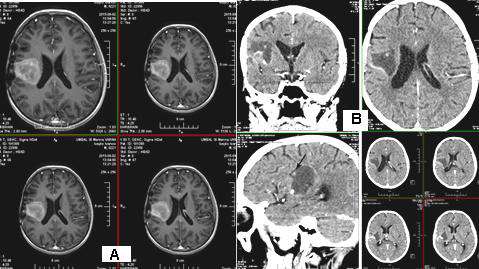

A 73-year-old patient after fibrobronchoscopy (FBS) with histologically and immunohistochemically (IHС) proven small cell lung cancer (SCLC) (T4 N1 M1/pleural) was presented. First-line chemotherapy (Ch) (Cisplatin and Etoposide) were performed. CT of the lung after 6 cycles of Ch - Tumor lesion of the right lobe bronchus with infiltration of the pleura - without dynamics. No secondary changes are reported bilaterally. Mediastinum - without enlarged lymph nodes bilaterally. A small discrete effusion in the right pleura was reported. CT of the brain - No secondary changes in the brain parenchyma. Ventricular system - unexpanded (Figure 1).

Intensity-modulated prophylactic whole-brain radiotherapy (WBRT) with daily dose (DD) 3 Gy up to total dose (TD) 30 Gy/ Biologically equivalent dose (BED) 38 Gy/5 times per week was performed (Figure 2).

Three months after WBRT, the patient complained of difficulty in balance and weakness of the right limbs. CT of brain with venous contrast - Parenchymal brain pathology is not visualized subtentorially. Edema zones temporoparietally and occipitally in the left cerebellar hemisphere, without visible nuclei of metastases are reported. Ventricular system and basal cisterns - undilated, without dislocation. Mild cortical atrophy bilaterally temporally is visualized (Figure 3).

Figure 2: The Intensity modulated prophylactic whole-brain radiotherapy (WBRT) with daily dose (DD) 3 Gy up to total dose (TD) 30 Gy.

Figure 3: CT of the brain after 3 months of prophylactic WBRT - Edematous areas temporoparietally and occipitally in the left cerebral hemisphere.

MRI of the brain (Figure 4) - Against the background of advanced changes in chronic ischemic disease of the small vessels, in the left parietal extensive cerebral edema, mild compression of the body of the left lateral ventricle. Post-contrast scans lack pathological capture of the contrast material. Infratentorial without evidence of pathological lesions. Conclusion - The MR finding corresponds to subacute changes after RT, without data on the presence of radionecrosis and without data on metastases. The patient was hospitalized with a worsened general condition and complained of fatigue, dizziness, hemiparesis of the right limbs and central involvement of the right facial nerve. Despite anti-edema and antiinflammatory therapy, the patient exits after 18 days.

Prophylactic whole-brain radiotherapy (PWBRT)

The whole-brain radiotherapy (WBRT) is conducted for two therapeutic purposes - preventive or prophylactic and curative. PWBRT is a standard approach in the limited or advanced stage of small cell lung cancer (SCLC) in clinical remission after systemic chemotherapy (Ch) and local pulmonary radiotherapy (RT). Without PWBRT, 60% of SCLCs develop brain metastases (BM), and they are reduced to 20% after it was performed [10]. PWBRT is also recommended for non- small cell lung cancer (NSCLC) [11-15], in which a significant reduction in BM of 18% to 8% without improved overall survival (OS) has been achieved [16] in contrast to SCLC, where OS is significantly increased [17,18]. The purpose of PWBRT is to destroy microscopic metastatic tumor cells in the brain before their clinical manifestation. Radiation brain effects after PWBRT are divided into acute, subacute and chronic [19]. Acute side effects occur during or one to two weeks after completion of PWBRT. They are expressed by general fatigue, alopecia and symptoms associated with increased cerebral edema - headache, nausea, focal brain deficits, a pronounced mental change [20]. These acute symptoms gradually subside in a large proportion of patients. On MRI, diffuse cerebral edema is visualized [21]. Subacute symptoms develop immediately after the completion of RT or three months after its completion. They are relatively rare and limited, mainly to drowsiness syndrome and less commonly as leukoencephalopathy [20]. 3 months after 10x3Gy PWBRT, the condition of a 73-yearold SCLC patient, who underwent 6 courses of Ch (Cisplatin and Etoposide) deteriorated. CT and MRI visualize extensive cerebral edema in the left hemisphere, without brain metastases (Figure 3 & 4). In children with leukemia after PWBRT, there is a “radiation somnolence syndrome” characterized by somnolence often associated with headache, nausea, vomiting and sometimes fever. The necessary treatment is the administration of corticosteroids, but it should be noted that these complaints may resolve spontaneously [22]. Somnolence is more common in children with PWBRT with concomitant chemotherapy (methotrexate/ intrathecal) [23]. Pathophysiologically, this somnolent syndrome is associated with transient demyelination of the white matter. On the other hand, it should be noted that leukoencephalopathy is considered a more severe manifestation of demyelination and may be fatal. These changes in white matter are much more common in adult patients with concomitant chronic cerebrovascular ischemia [20]. Symptoms are usually mild and stabilize or resolve. Imaging - CT and MRI with intravenous contrast varies from diffuse cerebral edema to increased accumulation of contrast [21]. In the presented adult patient it can be seen that against the background of antiedema medication treatment (Dexamethasone and Mannitol), the symptoms was not transient, on the contrary, they worsen (Figure 3 & 4). Subacute encephalopathy usually begins two or three months after cerebral RT but may occur 2 weeks to 4 months after completion of PWBRT. It is usually seen in patients with SCLC after chemotherapy of the primary tumor. The pathogenesis of subacute encephalopathy is due to demyelination due to damage to the oligodendroglia with subsequent involvement of the myelin sheaths [22]. The progression of these changes leads to late effects manifested by radionecrosis [23-25]. Tissue necrosis is a distinct syndrome of radiation toxicity, thought to be the consequence of vascular endothelial cell damage, resulting in fibrinoid necrosis of small vessels and direct brain parenchymal necrosis. Occlusion of small blood vessels results in focal coagulative necrosis, capillary leakage, and demyelination of the surrounding brain parenchyma [26,27]. The relationship between PWBRT and late brain toxicity was analyzed in 264 patients with limited stage SCLC [28]. Patients are divided into 3 arms depending on the DD and the TD: 10 fractions up to TD 25 Gy; 18 fractions up to TD 36 Gy and hyperfractionated RT ( two daily fractions) with 24 fractions up to TD 36 Gy. Neurological changes are reported after 6 months and 12 months of PWBRT. After 1 year, neurotoxicity was established in 60% of patients after TD 25 Gy and in 80-90% after TDs 36 Gy.